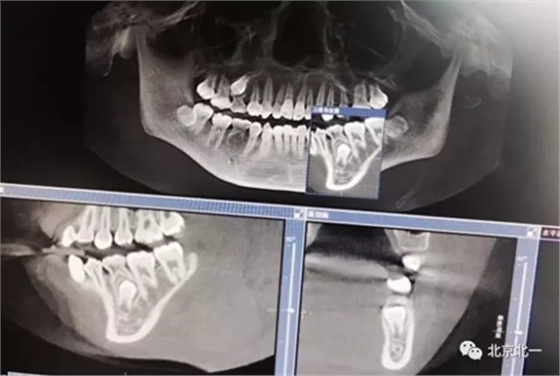

術(shù)中有絲分裂